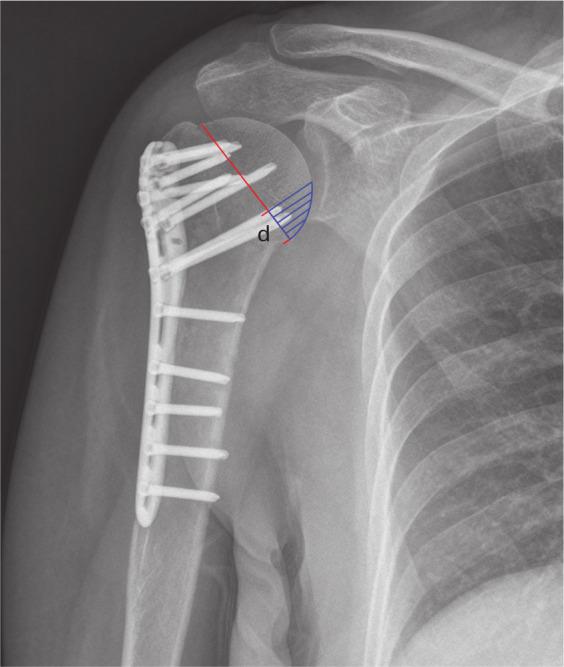

Data from 203 patients (63 males and 140 females) with a mean age of 62 years (22 to 89) were analyzed. In 49 fractures, the calcar screw was considered to be malpositioned; in 154 it was in the optimal position. The rate of malpositioning was therefore 24% (49/203). No preoperative risk factor was found for malpositioning of the calcar screws. Only the neck-shaft angle was found to be related to the risk of screw malpositioning in a multivariate model (with an AUC of 0.72). For the fractures in which the neck-shaft angle was reduced to between 130° and 150°, 91% (133/46) of calcar screws were in the optimal position.

The neck-shaft angle is the key factor for the appropriate positioning of calcar screws when treating a proximal humeral fracture with a locking plate. We recommend reducing the angle to between 130° and 150°. Cite this article: 2020;102-B(12):1629-1635.